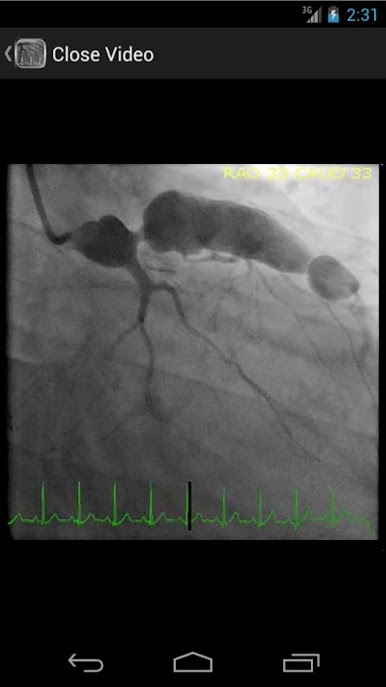

* Searchable database containing more than 30 videos (coronary angiograms, ventriculograms, and aortograms) of both common and rare findings in the cardiac catheterization lab

CathSource provides a detailed overview of important cardiac catheterization and angiography topics, incorporating educational images/videos as well as reviews of pertinent medical literature. CathSource is the ideal application to assist you in understanding and recognizing cardiovascular pathology in the catheterization lab.